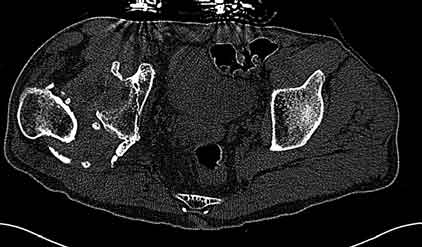

Уважаемые коллеги, пациент 30 лет, 4 года назад попал под поезд, ампутация обеих голеней в в/3, подвздошный вывих бедра (теперь застарелый). несмотря на такую ситуацию, пациент вполне прилично ходит и объем движений в неоартрозе близок к неповрежденной стороне. Основная жалоба - боль при нагрузке и в покое. Планируем двухэтапное лечение: резекция шейки, мобилизация проксимального отдела бедра, низведение бедра АВФ, вторым этапом б/ц эндопротезирование. Как поступить с головкой, вроде бы при протезировании можно будет обойтись без пластики, или ошибаюсь? Оставить ее там, где она есть? Другие варианты лечения.